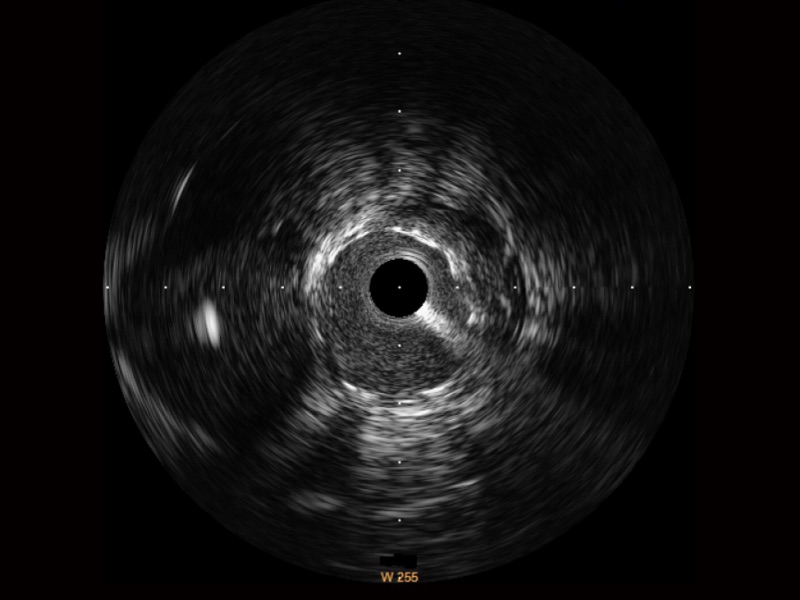

• 银河优越会宽频IVUS图像

• 传统IVUS图像

对比传统IVUS导管成像,银河优越会宽频IVUS图像的近场支架梁显影更细腻,远场中膜外血管仍清晰可辨,兼顾远中近,兼顾分辨力与穿透深度